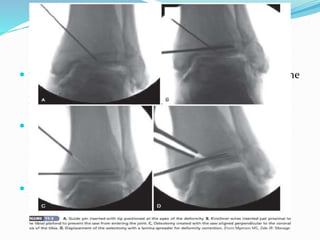

 Direct the apex of the osteotomy toward the

intraarticular deformity from the medial aspect of the

distal tibia.

 Use a Kirschner wire aimed at the apex of the

deformity as a guide to the plane of the osteotomy.

 Insert three additional Kirschner wires parallel to the

joint surface portion of the tibial plafond within the

subchondral bone just under the articular cartilage at

the apex of the plafond angulation to prevent

penetration of the saw blade

 with a wide osteotome gradually bend the plafond until the

medial tibial articular surface is parallel to the intact

portion of the distal lateral tibia.

 Insert a lamina spreader into the cortical gap to hold the

correction while allograft cancellous bone chips are

inserted into the defect under fluoroscopic guidance to

maintain a parallel joint surface.

 Secure the osteotomy with a locking plate to serve as a

buttress to ensure that the allograft remains in place.